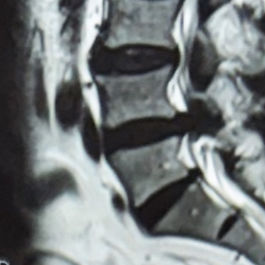

Spinal Decompression Surgery

The spine shows spinal stenosis at the level of the L4-5.